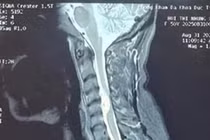

Tại bệnh viện K, anh H được các bác sĩ khám và chụp cộng hưởng từ, phát hiện khối u tủy cổ vị trí cổ cao (C3) nằm tại vị trí phức tạp, cần điều trị để loại bỏ nhanh chóng, tránh nguy cơ mất chức năng rễ thần kinh, dẫn tới yếu liệt chi hoặc rối loạn cảm giác lâu dài.

u-tuy-co.jpg